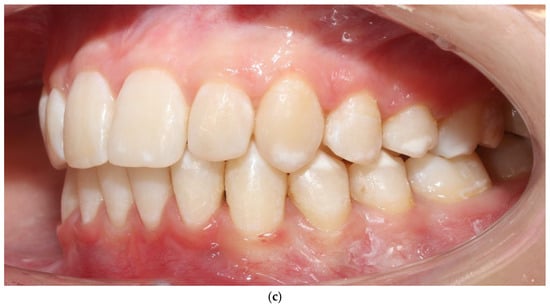

The vestibular soft-tissue phenotype appeared thicker, with reduced translucency and a more convex gingival contour. Gingival margin stability was maintained throughout therapy, and no recession, bleeding, or inflammation was present (Figure 4a–c). Outcome assessment in this case report is primarily qualitative and based on standardized clinical photography and clinical phenotype indicators (defined by periodontal probe transparency through the gingival margin), without quantitative soft-tissue thickness measurements.

Figure 4.

Patient 1 after treatment (a–c).

3.2. Patient 2—Soft-Tissue and Intra-Arch Control Outcomes

Because BPS was applied only in the maxillary arch, this patient provided an intra-arch control model under identical biological conditions. The maxillary BPS arch appeared to show features consistent with thickening of the vestibular phenotype, increased soft-tissue resilience, and reduced root translucency. In contrast, the mandibular control arch (treated with conventional biomechanics) appeared to retain a thin, translucent, and flattened phenotype. These qualitative clinical observations from both patients and both arches, including the intra-arch control, are summarized in Table 1.

Gingival phenotype was assessed using a standardized periodontal probe transparency test and evaluation of tissue resistance. No recession, pathological probing depths, or BOP were recorded. Although no ultrasonographic or transgingival thickness measurements were collected, the photographic changes were reproducible and consistent with recognized clinical indicators of phenotype thickening.